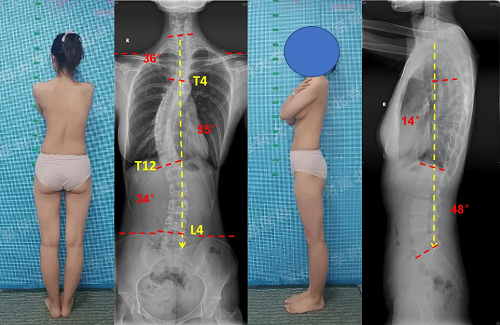

典型病例